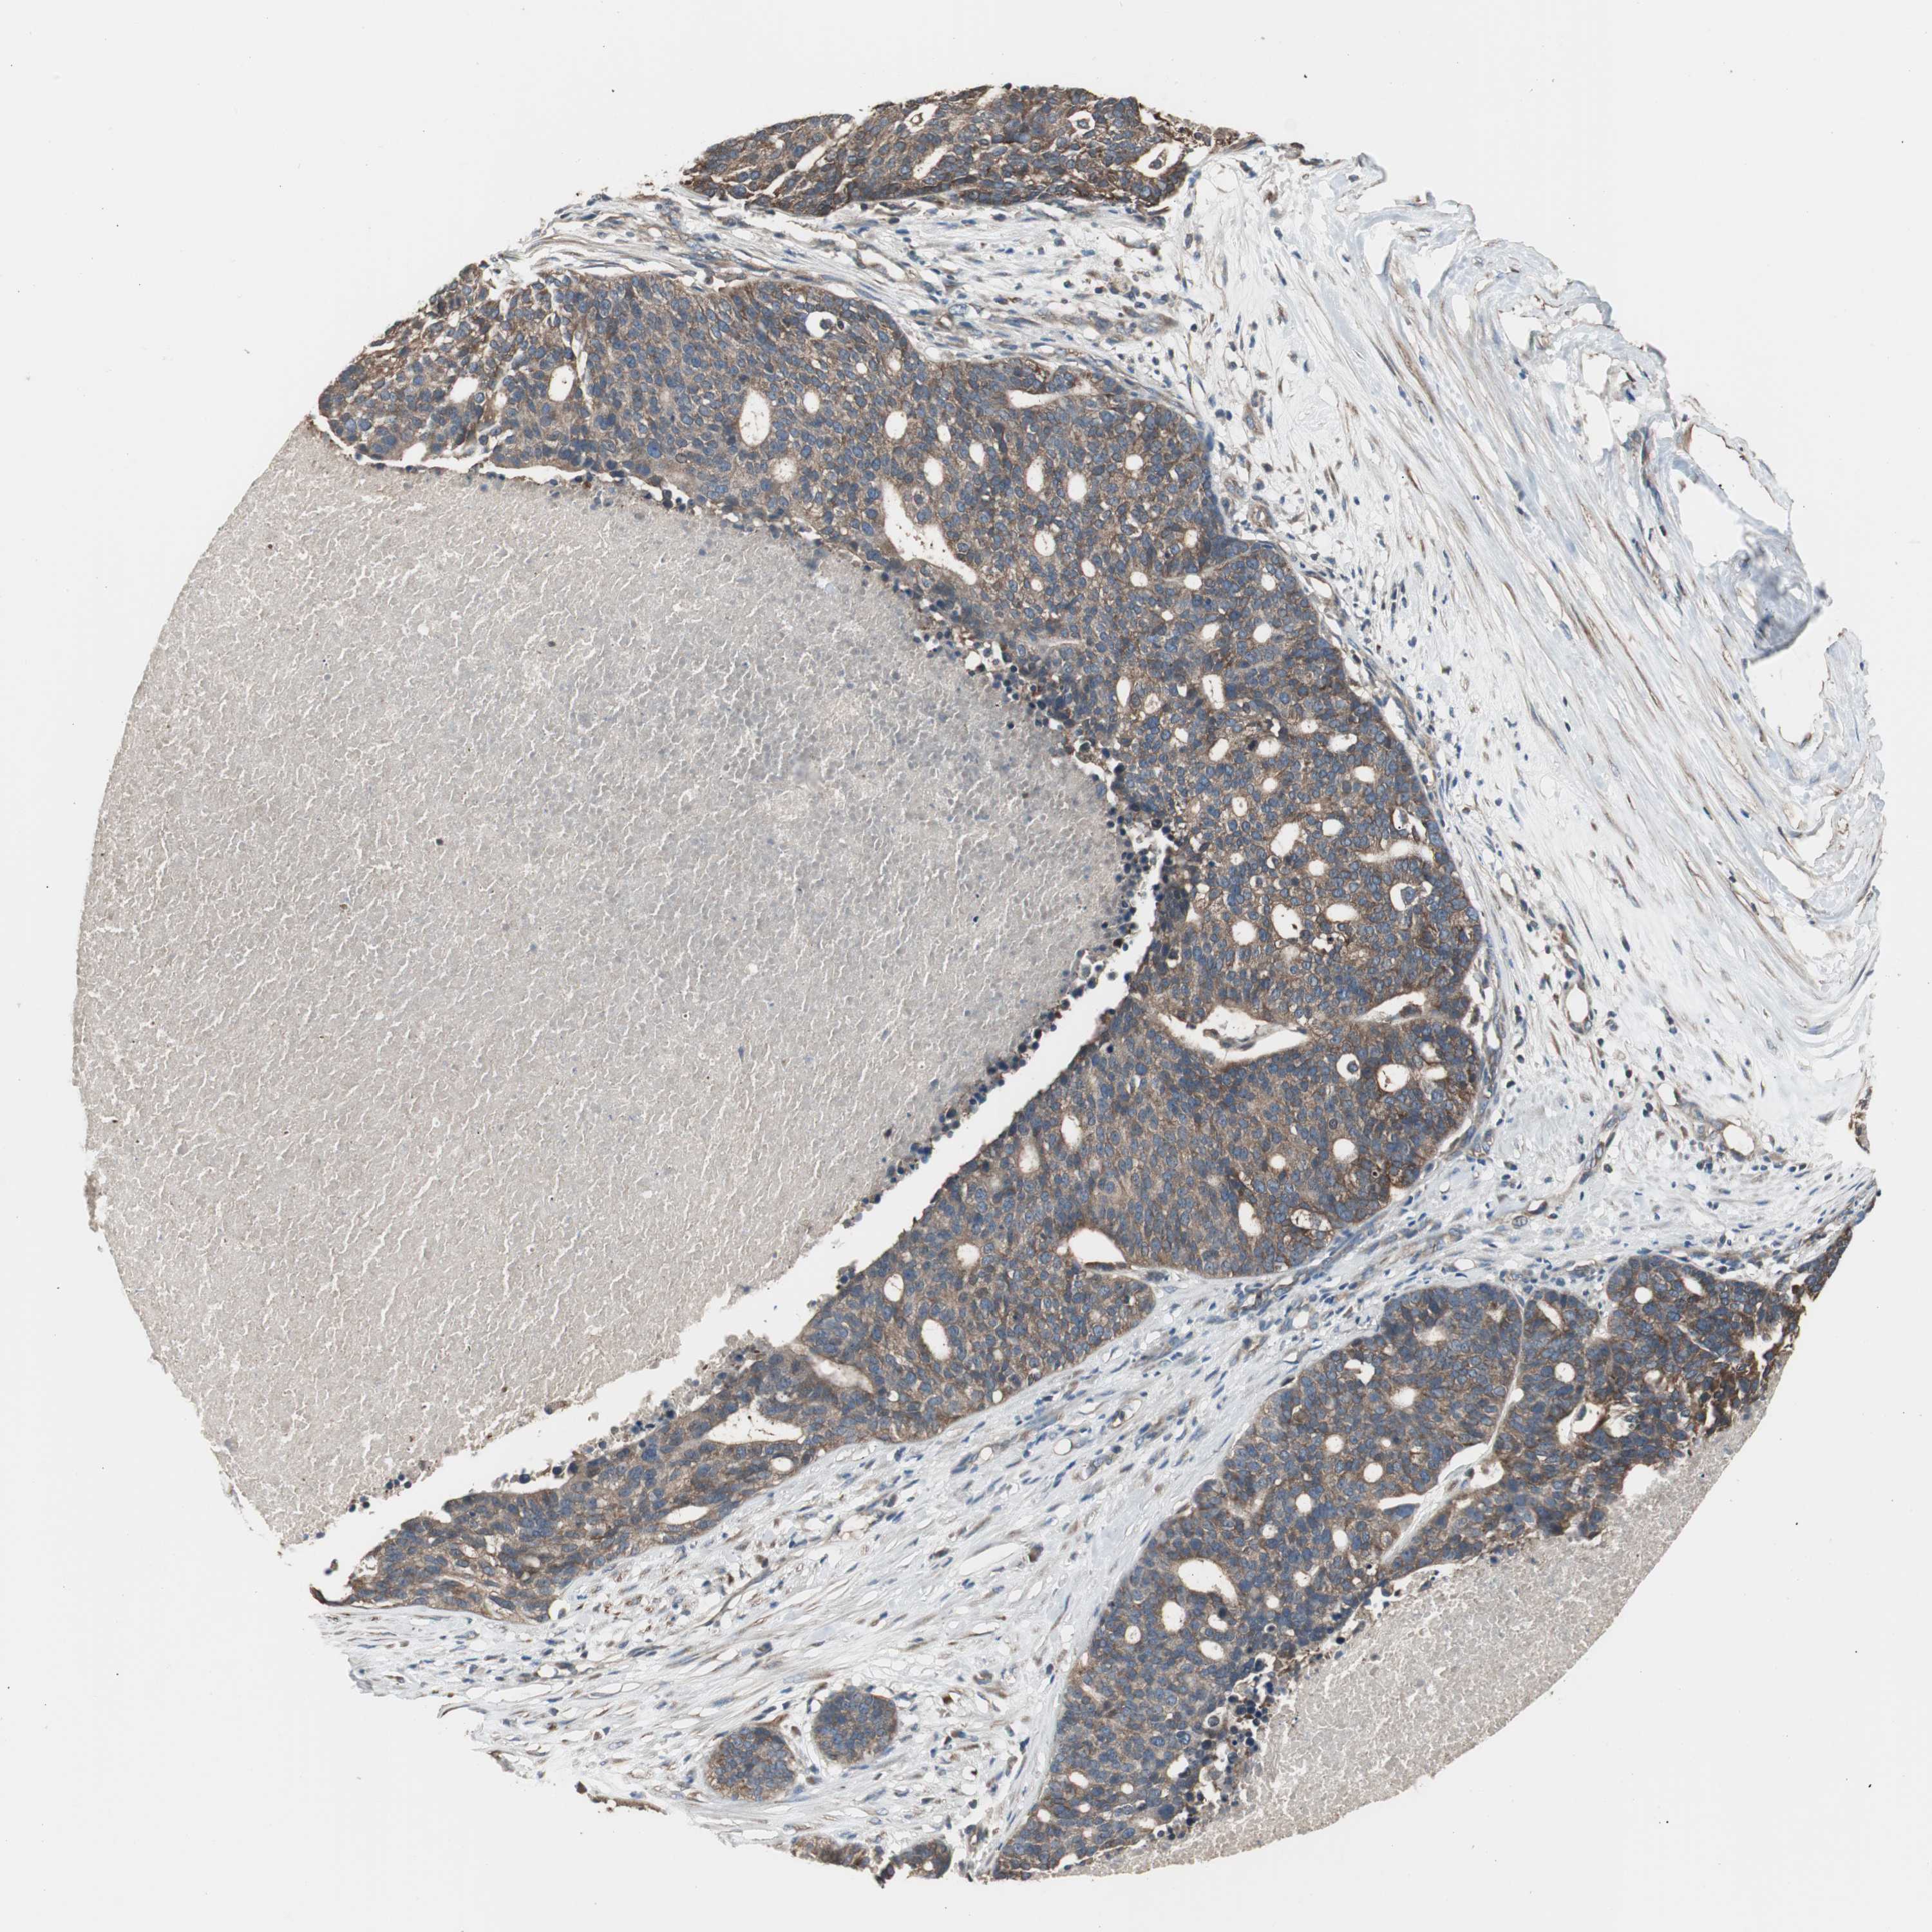

OVARIAN CANCER - Protein expressioni

A mouse-over function shows sample information and annotation data. Click on an image to view it in a full screen mode. Samples can be filtered based on level of antibody staining by selecting one or several of the following categories: high, medium, low and not detected. The assay and annotation is described here.

Note that samples used for immunohistochemistry by the Human Protein Atlas do not correspond to samples in the TCGA dataset.

Antibody stainingi

Antibody staining in the annotated cell types in the current human tissue is reported as not detected, low, medium, or high, based on conventional immunohistochemistry profiling in selected tissues. This score is based on the combination of the staining intensity and fraction of stained cells.

Each image is clickable and will lead to virtual microscopy that enables deeper exploration of all samples and also displays staining intensity scores, fraction scores and subcellular localization as well as patient and tissue information for each sample.

Antibody HPA006872

Staining

High

Medium

Low

Not detected

Intensity

Strong

Moderate

Weak

Negative

Quantity

>75%

75%-25%

<25%

None

Location

Nuclear

Cytoplasmic/membranous

Cytoplasmic/membranous,nuclear

Cystadenocarcinoma, serous, NOS

Carcinoma, endometroid

Carcinoma, NOS

Cystadenocarcinoma, mucinous, NOS